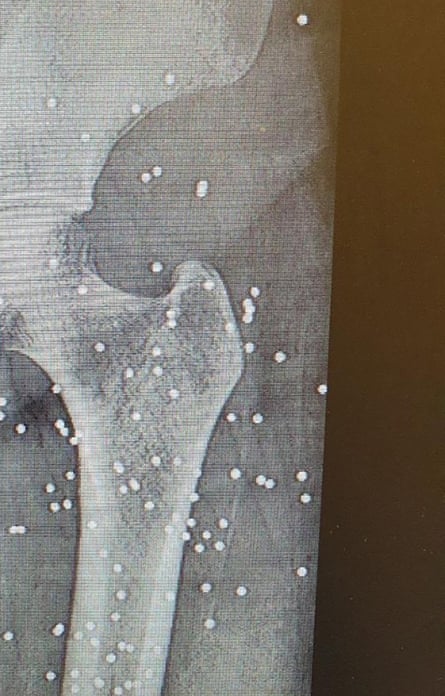

Up until a few hours earlier, doctors and patients were still sending me photos on WhatsApp; pellet wounds to the back, the hands, the head. Painful injuries, frightening injuries – but survivable. The kinds of wounds that could be treated, that suggested the violence still had limits. Then, at eight o’clock, everything went dark. Internet, mobile phones, messages, maps – all gone.

The patients coming in now were not hit by pellets – they had been shot with live ammunition. War bullets. These were not warning shots. These were bullets designed to pass through the body. Bullets that entered on one side and exited from the other.